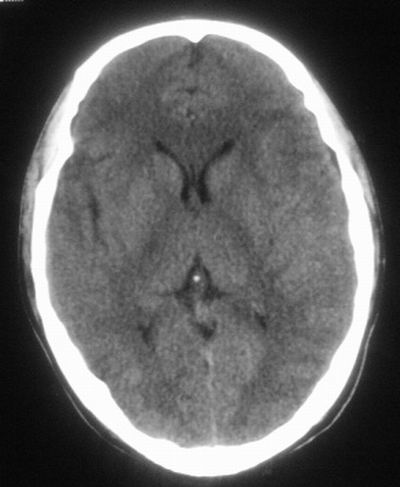

治疗三天后复查ct片示:

治疗三天后复查ct:除左侧额顶叶血肿外。左侧额叶另见片状低密度灶,密度不均匀,境界不清;考虑脑梗塞。